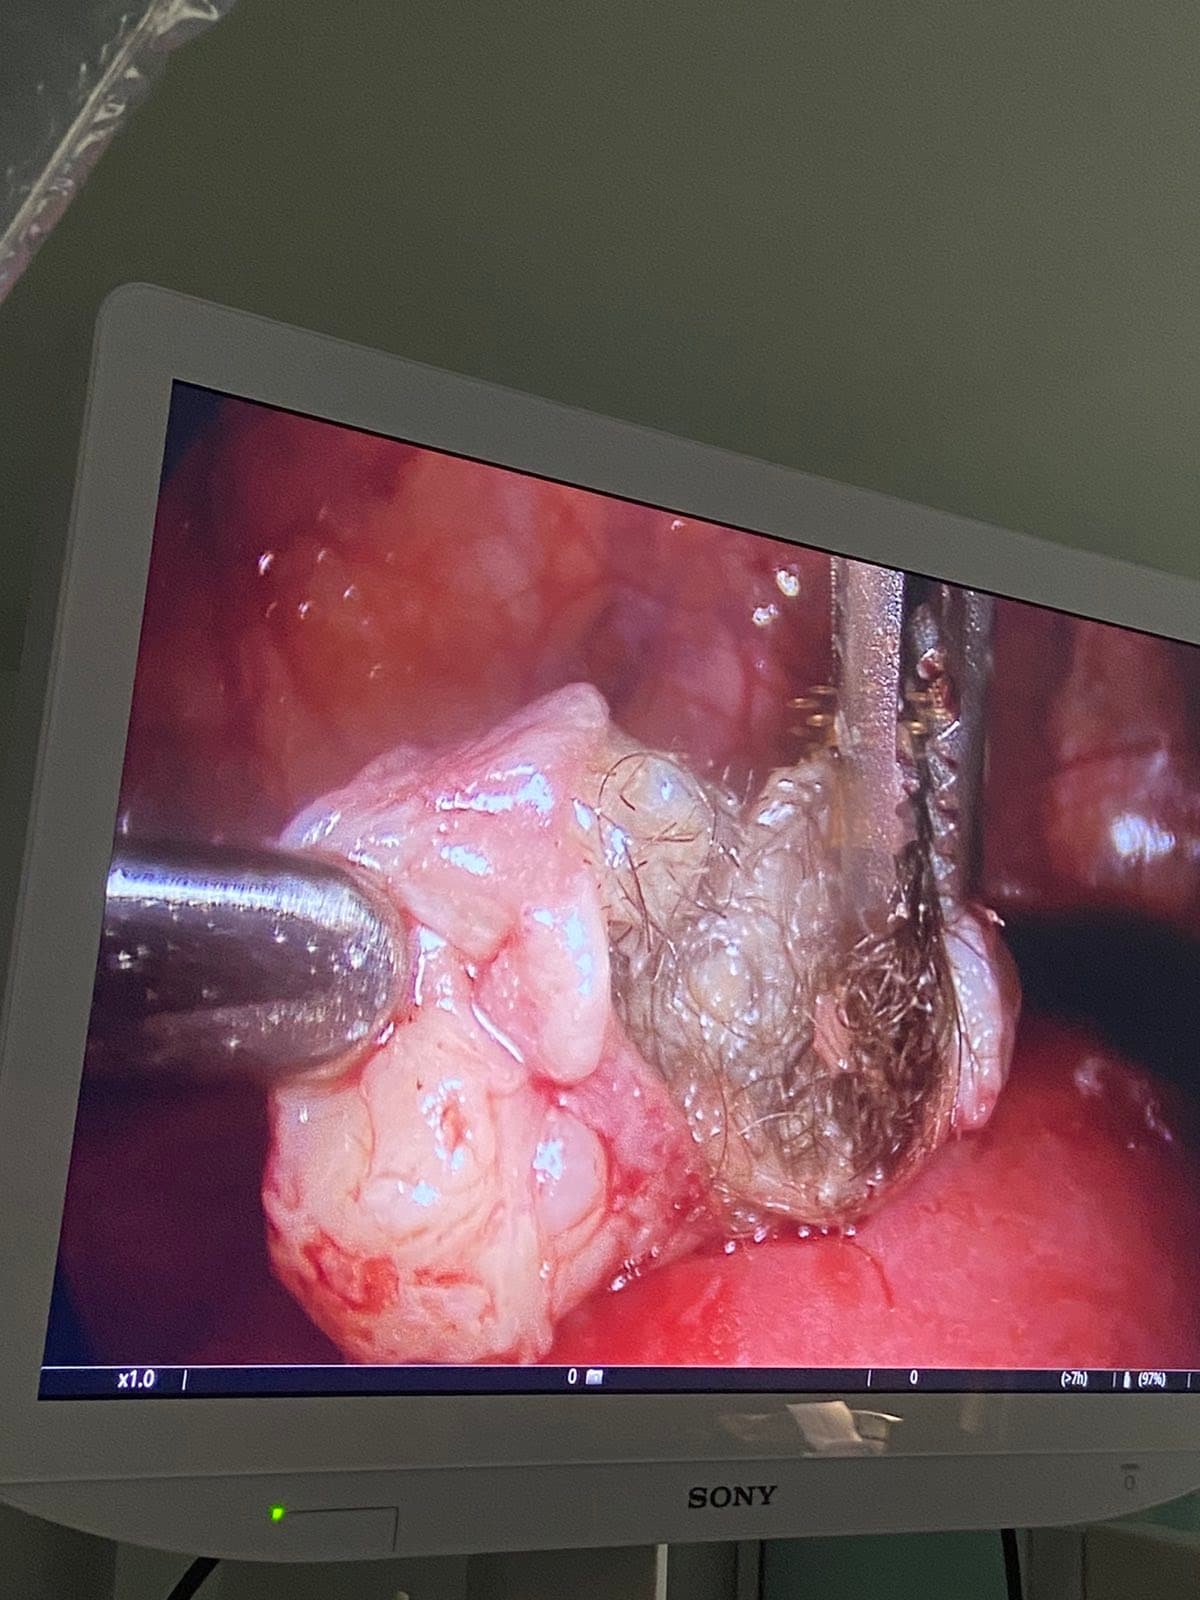

Μαιευτήρας Γυναικολόγος Βόλος Λάρισα | Ρομποτική Χειρουργική Da Vinci X